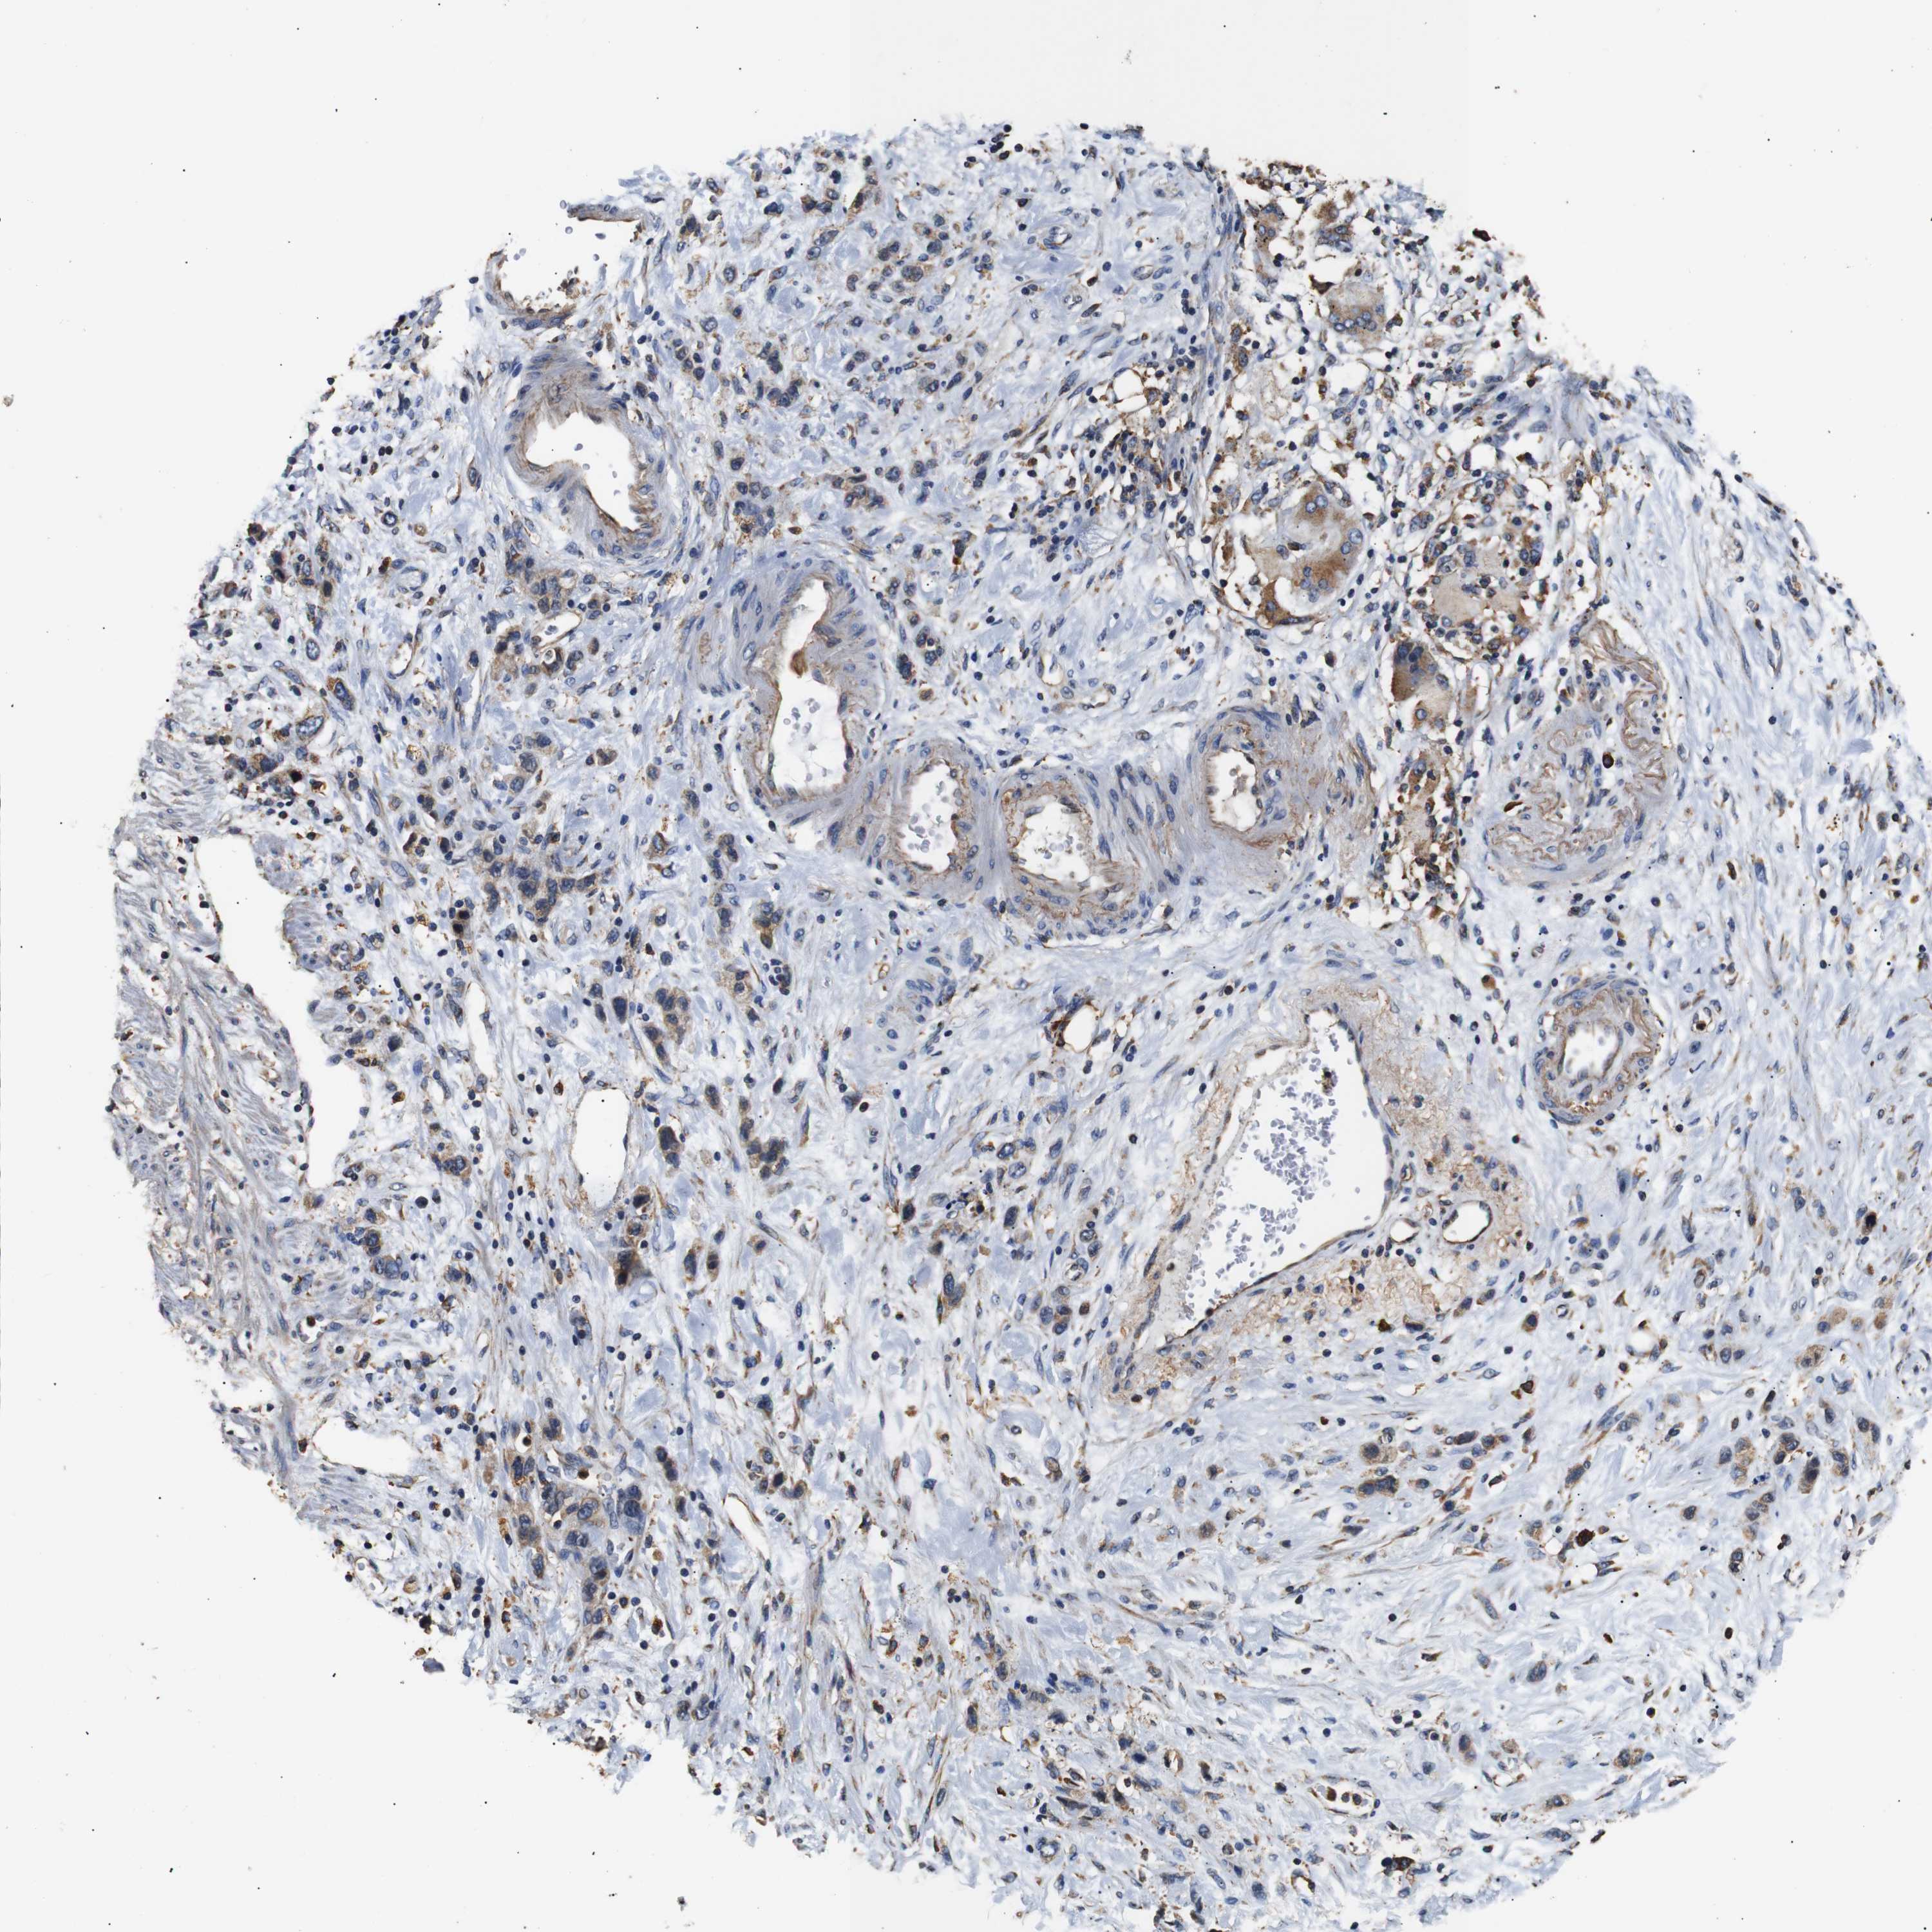

STOMACH CANCER - Protein expressioni

A mouse-over function shows sample information and annotation data. Click on an image to view it in a full screen mode. Samples can be filtered based on level of antibody staining by selecting one or several of the following categories: high, medium, low and not detected. The assay and annotation is described here.

Note that samples used for immunohistochemistry by the Human Protein Atlas do not correspond to samples in the TCGA dataset.

Antibody stainingi

Antibody staining in the annotated cell types in the current human tissue is reported as not detected, low, medium, or high, based on conventional immunohistochemistry profiling in selected tissues. This score is based on the combination of the staining intensity and fraction of stained cells.

Each image is clickable and will lead to virtual microscopy that enables deeper exploration of all samples and also displays staining intensity scores, fraction scores and subcellular localization as well as patient and tissue information for each sample.

Antibody HPA012616

Staining

High

Medium

Low

Not detected

Intensity

Strong

Moderate

Weak

Negative

Quantity

>75%

75%-25%

<25%

None

Location

Nuclear

Cytoplasmic/membranous

Cytoplasmic/membranous,nuclear

Adenocarcinoma, NOS

Adenocarcinoma, High grade